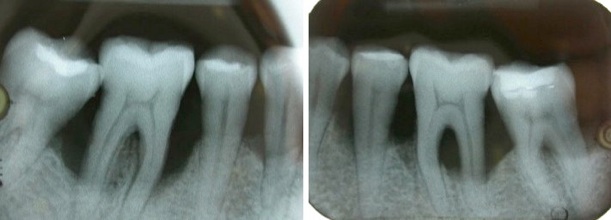

Gingivites = inflammation gingivale sans atteinte osseuse , complètement réversible à l'état sain par une reprise correcte de l'hygiène dentaire et détartrage. Les saignements au sondage ou au brossage dentaire sont provoquées par les bactéries contenues dans la plaque dentaire et le tartre.

Parodontite = perte d’attache ( os , gencive, ligaments , cément radiculaire) , partiellement réversible par traitement non chirurgical ( détartrages et surfaçages radiculaires ) ou chirurgical et reprise correcte de l'hygiène dentaire et maintenance parodontale régulière . La perte osseuse horizontale est irréversible. On peut régénérer l’os partiellement dans le cas des lésions osseuses verticales.

2.Pour le parodonte épais, la résorption osseuse est accompagné par une faible récession gingivale et de la formation d’une poche parodontale

Dans les poches parodontales, les bactéries trouvent les conditions idéales pour se multiplier et sécrètent des toxines.

En fonction de la profondeur des poches parodontales on décide du type de traitement :

1.moins de 5 mm = non chirurgical ( détartrages et surfaçages radiculaires )

2.plus de 5 mm = chirurgical